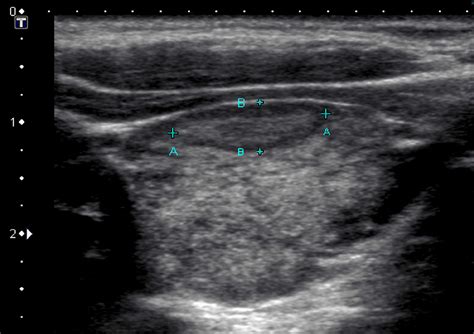

On the other hand, a sonogram is the result of that technology. It is the actual image produced by the ultrasound machine. Think of it this way: the ultrasound is the process or the machine, while the sonogram is the “photograph” or the output that the doctor analyzes to make a diagnosis.

- Sonogram: The image, the data visualization, or the report generated by the ultrasound machine.

The evolution of ultrasound technology has been one of the greatest advancements in non-invasive diagnostics. The clarity of the sonogram you receive today is lightyears ahead of what was available even two decades ago. High-definition imaging and 3D/4D ultrasound capabilities allow doctors to visualize anatomy with incredible precision, leading to earlier detection of potential health issues and better outcomes for patients. Understanding the nuance between ultrasound vs sonogram helps you better appreciate the technological marvel that allows doctors to see inside the body without a single incision.